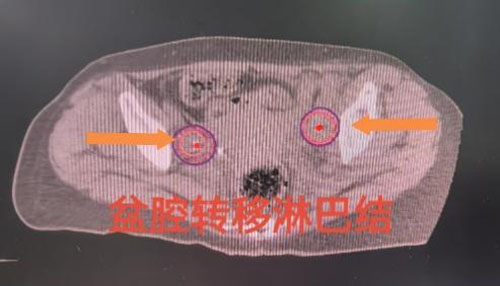

刘红教授和妇产超声科王翠菊教授团队为来访专家展示了两例疑难病例插植放疗操作的全过程。一名患者为宫颈癌IIIC1R期盆腔闭孔区域淋巴结转移。淋巴结转移是宫颈癌最常见的转移路径,同时也是影响宫颈癌患者预后最主要的危险因素之一,转移淋巴结通常需要更高的放疗剂量才能获得更好的局部控制效果。通过该项技术,在后装治疗过程中可以同时实现宫颈肿物和转移淋巴结的同步推量照射,在保护危及器官的同时,给予转移淋巴结更高的放射剂量,从而获得更好的肿瘤局部控制效果。另一名患者为宫颈癌术后膀胱后壁肿物复发。肿物体积越小,治疗效果越好,放疗的副损伤越小,但是,体积越小的肿物越难做到精准插植治疗。经腔内超声实时引导的插植技术,可以实现对微小肿物的精准定位,在确保不损伤膀胱的前提下,精准实现盆腔复发肿物的近距离放疗。